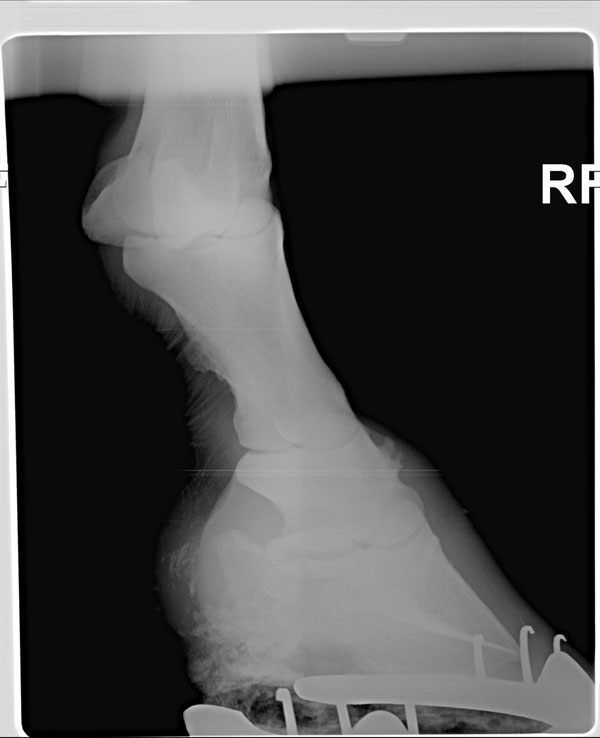

I have attached radiographs of my 16 year old gelding's right front pastern. He has been slightly lame for a month or so. We are trying to determine the treatment that would be best for him. I am alarmed at the bone spurs he has! I am trying to decide what course of action to take. We changed his shoes to increase ease of breakover and added pads. That has helped a lot. He seems better unless he is on very uneven ground or he makes a very sharp right turn. He is on Cosequin ASU and has been for some time. We are going to start Adequan IM and we are debating wether to do IRAP injections or HA injections. This gelding was also recently diagnosed with Cushingoid synDrOme and is on a very low dose of pergolide. He is my problem child at the moment!

Though there are signs of DJD in the pastern joint and remarkable bony proliferation in the bones of the pastern it is not clearly a cause of lameness. You may occasionally find horses with changes above in sound horses. However in combination with the results of the nerve blocks this is pretty damning. Is the history and clinical course of the lameness also consistent with a chronic, progressive disease that worsens with exercise?